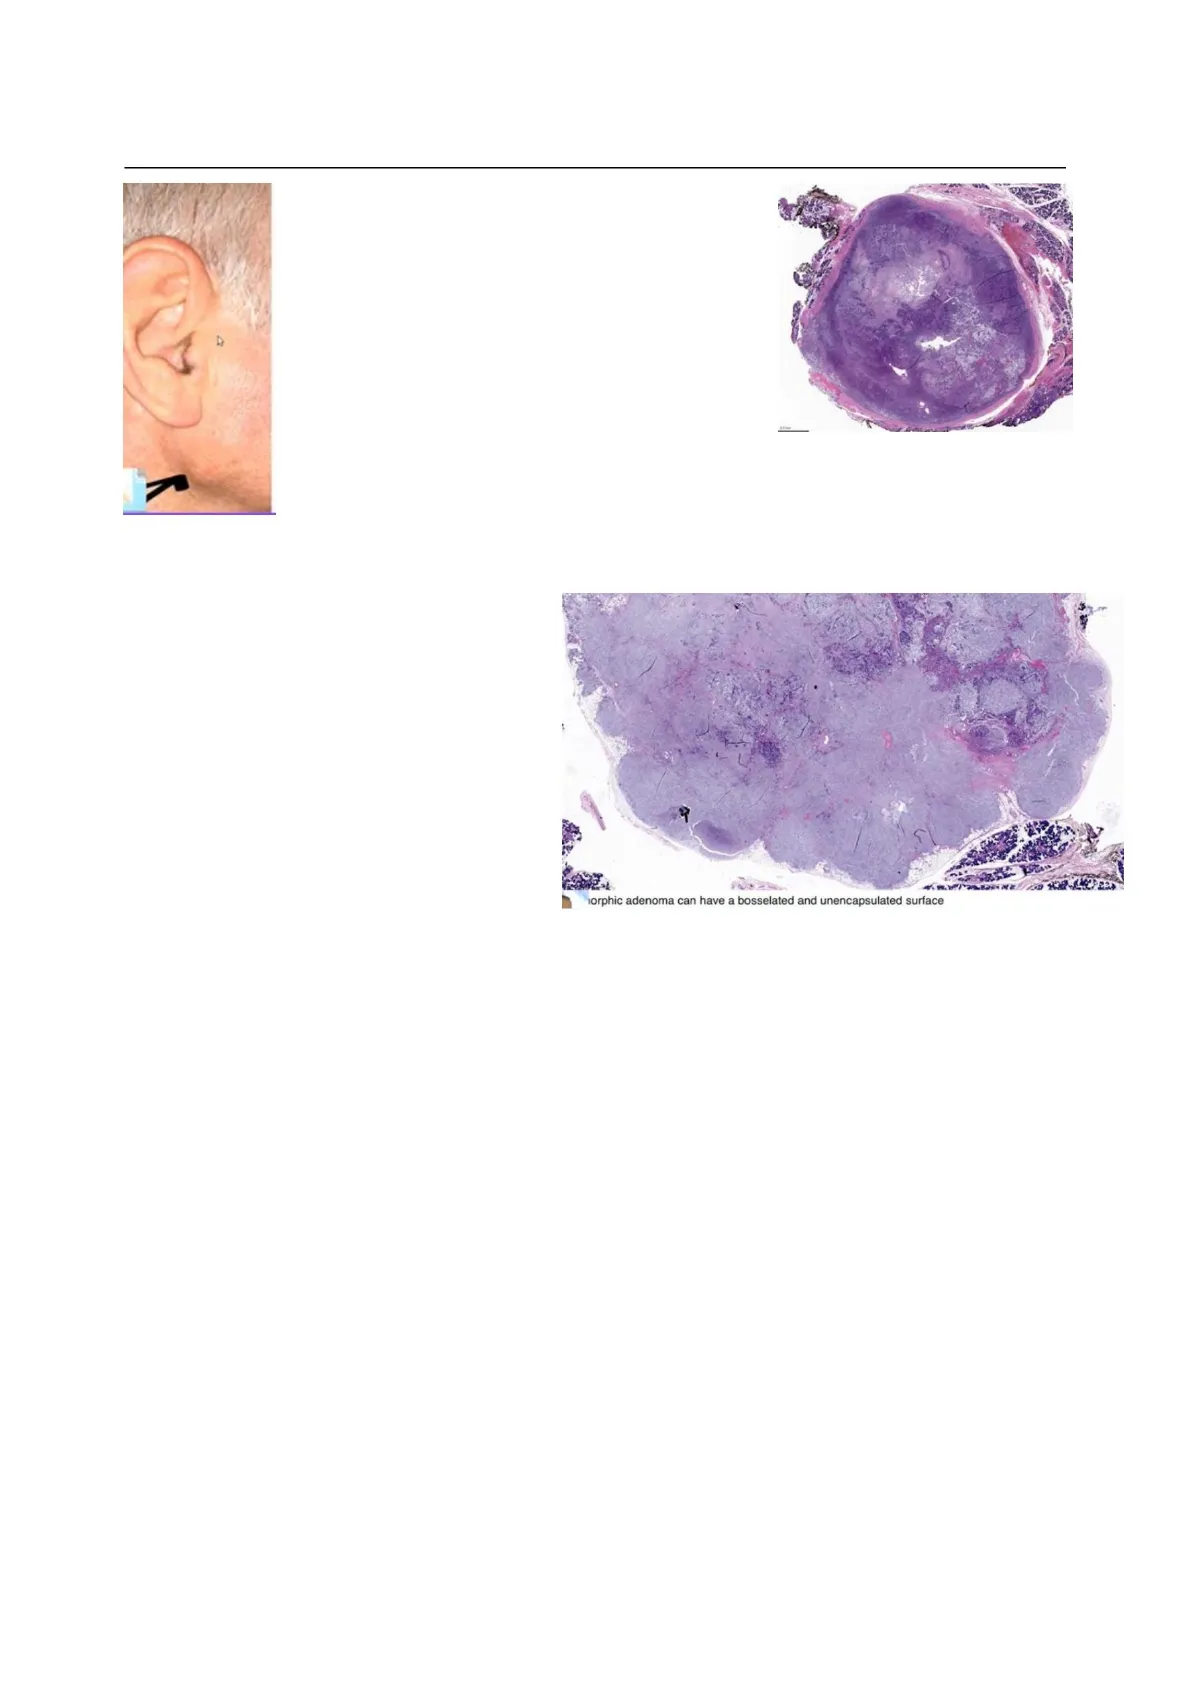

È il tumore più comune delle ghiandole salivari. Di solito appare nelle donne di mezza età. Si verificano più spesso nelle ghiandole parotidi, perché essendo più grandi è più facile trovare tumori al loro interno. Nell'immagine a sinistra possiamo vedere un grande rigonfiamento sulla ghiandola parotide inferiore all'orecchio.Machine Translated by Google Anatomia Patologica#25.2 - Prof. Alò - Tumori della ghiandola salivare Pagina 2 di 9 Nell'immagine centrale si vede il tumore asportato: la zona più bianca è la massa tumorale, ed è facilmente riconoscibile dal parenchima sano della parotide; il fatto che sia incapsulato e facilmente riconoscibile è caratteristico di un tumore benigno. In questo tipo di tumore, possiamo avere diversi tipi di cellule, ma tutte le cellule avranno caratteristiche di benignità, quindi un rapporto preservato tra nucleo, citoplasma e organelli, nessuna distorsione o cicatrice della membrana nucleare, ecc. , l'attività mitotica viene ridotta e viene conteggiata come il numero di cicli mitotici in un campo ad alta potenza. Se troviamo un basso numero di attività mitotiche, è anche un indicatore di benignità. La presenza di nucleoli vacuolati, citologia blanda, piccoli nucleoli, strutture simili a condotti, sono tutti caratteristici dell'adenoma pleomorfo. Allo stesso modo, troviamo le cellule mioepiteliali In questa immagine possiamo vedere la spinta bordi, bordi arrotondati e nella parte inferiore nella parte sinistra e destra dell'immagine noi può identificare la presenza di una salivare normale ghiandola. Possiamo anche vedere la presenza di diversi colori: rosa, viola, viola chiaro e questi i colori significano che ci sono celle diverse, che si differenzieranno rispetto alla condizione iniziale, ma saranno sempre benigni. 9 orphic adenoma can have a bosselated and unencapsulated surface -Superficie esterna bugnata, spesso con sporgenze simili a lingue (pseudopodi). Tipicamente ha i seguenti componenti:

Il professore ha detto l'unica cosa che hai detto tu bisogna ricordare che a volte il le cellule possono essere viste all'interno dei vasi, ma se hanno caratteristiche mologiche di billianc he è difficile identificare; perché in questo caso lo siamo parlando di un tumore benigno. L'adenoma pleomorfo è un tumore trifasico con cellule duttali (epiteliali), mioepiteliali e stromali. componenti; la componente stromale è tipicamente condromixoide o mixoide. Myoepithelial Ductal Stroma phic adenoma is a triphasic tumor with ductal (epithelial), myoepithelial and stromal ents. the stromal component is typically chur.dro taxold it maxbid logy Dobbiamo osservare nel mioepitello come si presenta, le caratteristiche morfologiche di ogni singolo cellula e se la cellula di una ghiandola normale è vista nel tumore, e infine come appare lo stroma. In questo caso, e fare un caso di tumore maligno significa avere a che fare con un tumore benigno; invece lo stroma ha cellule differenziate e la cosa importante da vedere è che tra le cellule c'è è molta distanza il che significa che producono matrice e non proliferano. Quindi, per questo motivo, stiamo analizzando i tumori benigni. Ricorrente adenoma pleomorfo: numerosi noduli di varie dimensioni con caratteristiche istologiche tipiche del pleomorfo adenoma. Vuol dire che siamo di fronte una ghiandola su cui possiamo vedere più di uno isola umorale che hanno sempre il caratteristica di un tumore benigno che può spingere il tessuti che li circondano. current pleomorphic adenoma: numerous nodules of various size with typical histologic features pleomorphic adenoma Professore: Quello che voglio che tu sappia, è che se vedi superare i confini o spingere margini sei di fronte a un tumore benigno, invece se vedete i margini infiltrati significa che siete davanti ad un tumore maligno. Il tumore è caratterizzato dalle stesse caratteristiche, basta conoscere le caratteristiche dell'istologia normale del tessuto.